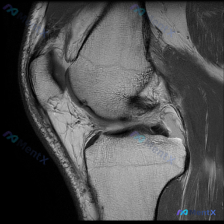

看到这个很有代表性的读片病例,整理出来和大家分享,这个临床-影像不匹配的情况其实临床工作中挺常见的。 病例基本信息 本次分析基于一张膝关节矢状位T1加权磁共振图像,临床提示存在「chondral abnormality(软骨异常)」,无其他病史、体征或检验结果提供。 影像基本观察(单张T1序列) 先...

看到一个有意思的影像读片问题,整理了完整的分析思路分享给大家。 病例/影像基本信息 这是一张单幅膝关节矢状位T1加权MRI影像,问题是观察图像中是否存在软骨异常。 影像本身特点:图像有明显噪声(颗粒感重),对比度一般,解剖结构轮廓可辨认,但精细细节分辨率受限,属于质量不佳的单幅影像。 系统性影像观察...

整理了一份很有参考意义的影像读片病例,核心问题是:这张膝关节MRI-T1序列矢状位图像上,能观察到软骨异常吗?把整个分析思路分享给大家。 一、影像基础信息 这是一幅标准的膝关节矢状位T1加权像,图像对比度良好,骨髓腔呈正常高信号(脂肪髓),皮质骨呈低信号,解剖结构显示清晰,无明显运动或金属伪影;图像...

遇到一个挺典型的读片问题,整理出来和大家分享一下思路: 病例背景 临床关注点:怀疑膝关节软骨异常,提供单张膝关节MRI矢状位T1加权像(T1WI)读片 影像基础评估结果 先把影像上能看到的情况理清楚: 1. 骨性结构:股骨远端、胫骨近端皮质连续,没有骨折;骨髓信号是正常脂肪骨髓的灰白色信号,没有局灶...

刚整理了一份有意思的膝关节MRI读片病例,临床提示观察到软骨异常,但单张T1加权矢状位影像却没看到明确异常,把分析思路整理出来和大家讨论。 一、病例基本影像信息 这是一张膝关节T1加权矢状位旁矢状位MRI图像,显示区域包括股骨远端、胫骨近端、髌骨、髌腱、Hoffa's脂肪垫和部分后交叉韧带,主要观察...

今天遇到一个有意思的读片问题:临床怀疑膝关节软骨异常,但提供的单张矢状位T1加权MRI读下来基本正常,整理一下分析思路和大家分享。 一、现有病例影像资料整理 这是一张膝关节矢状位T1加权MRI,图像质量清晰,信噪比良好,可见层面包含股骨远端外侧髁、胫骨近端、后交叉韧带、半月板前后角、髌韧带及Hoff...